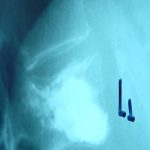

Η αντιμετώπιση η οποία εφαρμόζεται τις τελευταίες δύο δεκαετίες είναι η ενίσχυση των σπονδυλικών σωμάτων με έγχυση Poly-Μethyl-Μetha-Crylate (PMMA-«τσιμέντο») με χειρουργικές μεθόδους περιορισμένης επεμβατικότητας. Η τεχνική αυτή ονομάζεται «Κυφοπλαστική – Σπονδυλοπλαστική».Είναι δε μια ασφαλής και αποτελεσματική τεχνική η οποία αντιμετωπίζει άμεσα τον πόνο σε ποσοστό 95% και επιτυγχάνει διόρθωση της Σπονδυλικής Παραμόρφωσης και αποκαθιστά το ύψος του κατεαγότος σπονδύλου. Οι εγχύσεις αυτές πραγματοποιούνται στο χειρουργείο υπό συνεχή ακτινοσκοπικό έλεγχο, συνήθως υπό γενική αναισθησία και ο ασθενής παραμένει στο νοσοκομείο για μια ημέρα (εικόνα 2.α,β,γ).

Εικόνα 2-α,β,γ : Με την τεχνική του Baloon-Κυφοπλαστικής πραγματοποιήθηκαν Κυφοπλαστικές (έγχυση Poly-Methyl-Metha-Crylate (PMMA)-«τσιμέντο» σε ένα ή σε πολλά σπονδυλικά σώματα.